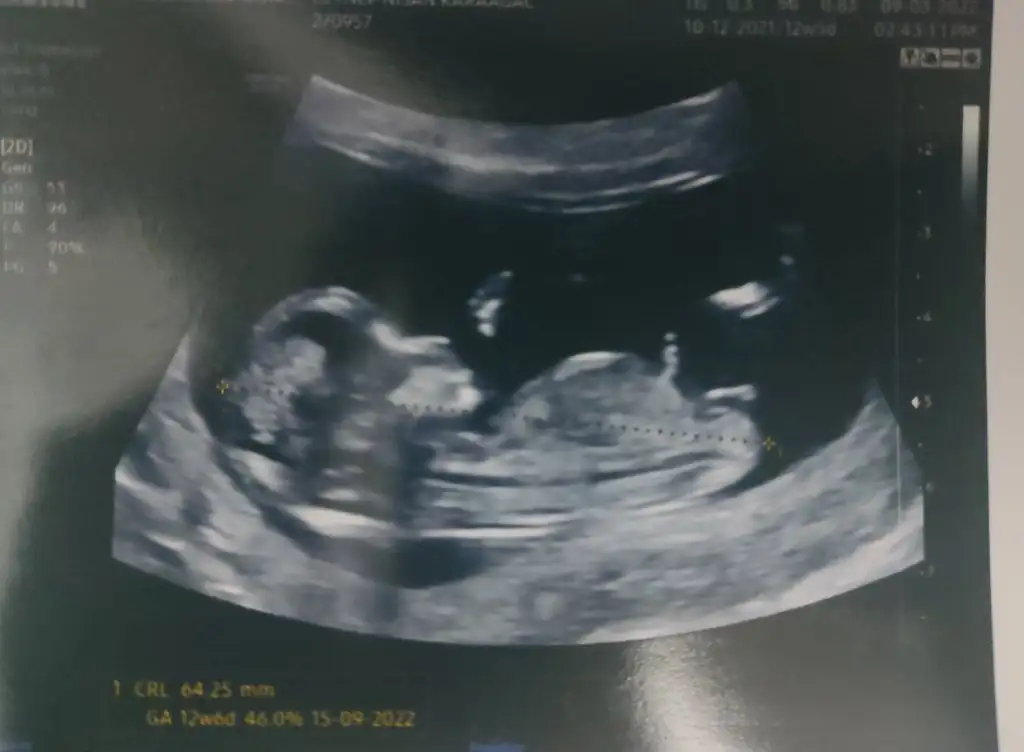

Nub a göre kız canımMerhaba, 13.hafta ultrason görüntüsüne göre cinsiyet tahmini yapabilir misiniz

Merhaba, 13.hafta ultrason görüntüsüne göre cinsiyet tahmini yapabilir misiniz?cinsiyeti ogrenebildiz mi ? Allah sağlıkla büyütmek nasip etsin.. benim bebeğim de 11 haftalık çok merak ediyorum yorumlar misinizzz

Benimde 13 haftalık ikili taramada erkege benzettim dedi ama görüntü net degil keseden anlayan cıkarmıMerhaba, 13.hafta ultrason görüntüsüne göre cinsiyet tahmini yapabilir misiniz?

Banada bakarmisiniz ben anlamadim pek 13 hafta burdaEki Görüntüle 3020419 nub teorisine aciklayan Bir resim bu.

Siz kendini de karsilastirabilirsiniz.

Bana bebeginiz kiz gibi geldi